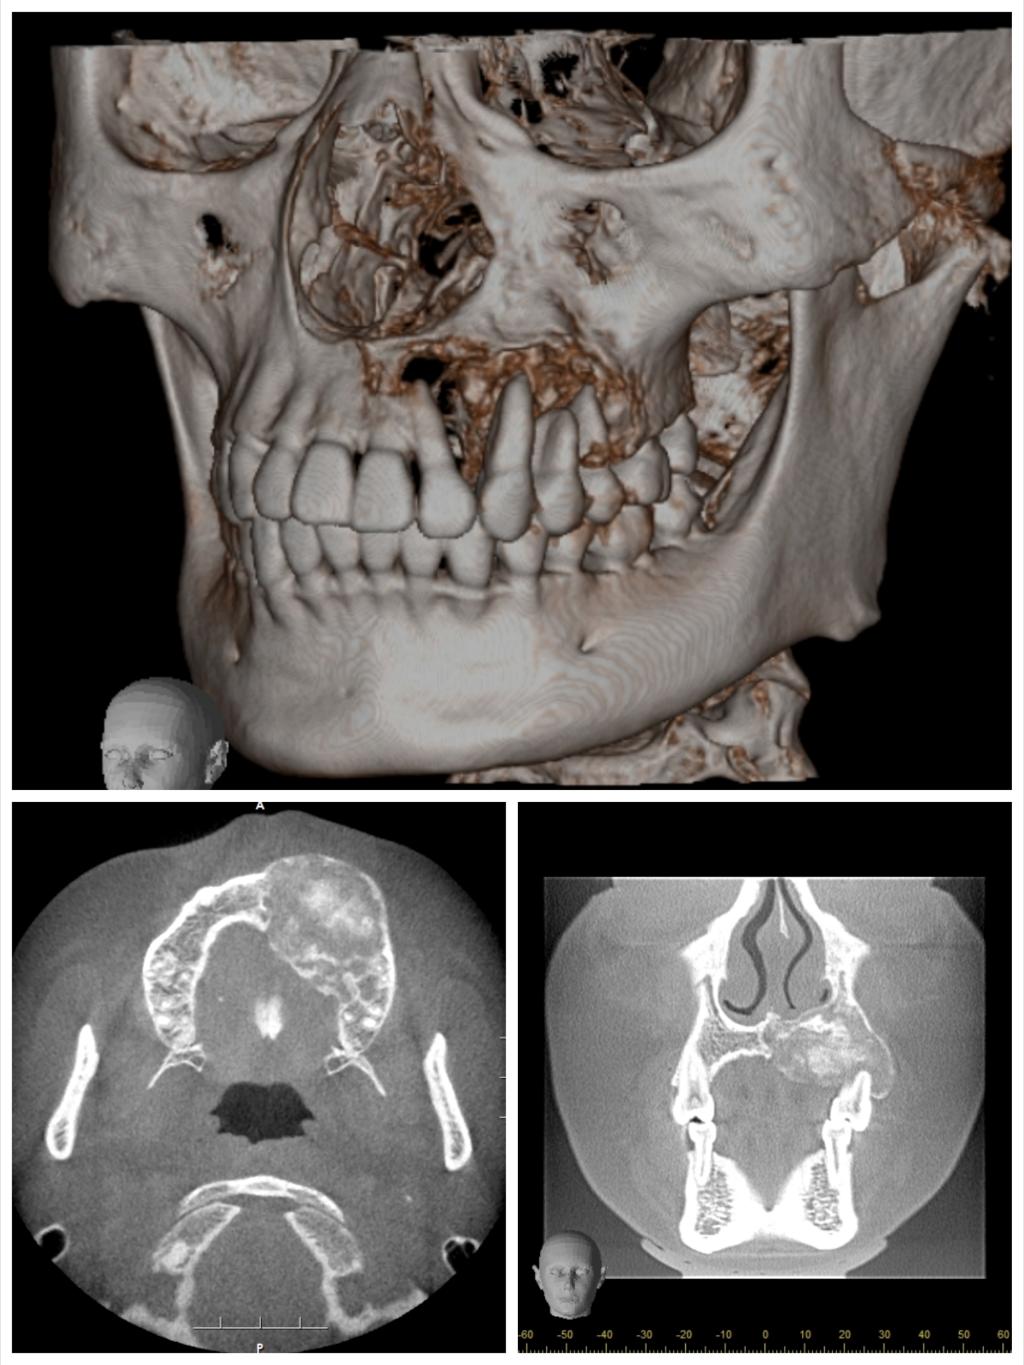

患者今年25岁,是一名年轻的母亲,1年前左侧上颌牙龈出现无痛性肿块,肿块逐渐增大,导致左侧面部畸形和牙松动。心急如焚的她咨询多家医院后,就诊口腔医院口腔颌面外科,口腔颌面外科主任吴亚东了解其病情后,制定了详细完善的个性化手术治疗方案,用血管化腓骨移植修复左侧上颌骨肿瘤切除后的缺损,既保证了术后不会因为硬组织缺失而导致面部塌陷,也能为后期种植牙修复提供足够的骨量。由于患者为年轻女性,为避免在面部留下明显的瘢痕,手术没有行上唇正中至鼻旁入路或下唇侧唇劈开入路,病灶切除及腓骨就位均在口腔内切口完成,但这也大大增加了手术难度。

本次手术历时6个小时,吴亚东团队精确切除了患者左上颌骨肿瘤,利用数字化血管化腓骨瓣及个性化钛网重新恢复了这位年轻妈妈的面型及上颌骨缺损。术后在口腔颌面外科护理团队的精心护理下,患者病情恢复良好,现已治愈出院。面型基本对称,移植的腓骨瓣存活良好。半年后,这位年轻的妈妈就可以利用“新的上颌牙槽嵴”进行种植牙恢复咀嚼功能。

目前,口腔医院完成血管化骨瓣移植修复重建下颌骨、血管化肌皮瓣修复软组织缺损已超百例,技术成熟,各类骨肌皮瓣存活率极高。但上颌骨肿瘤因临近鼻腔、上颌窦、眼眶等重要复杂结构,缺损的形态不规则,切除后缺损的修复有极大难度。上颌骨切除术后会导致口鼻瘘、面型畸形、语言及进食障碍、甚至对病人及其家属造成巨大的心理障碍。口腔颌面外科致力于解决患者的病痛,利用计算机辅助设计 / 计算机辅助制造(computer assisted design/computer assisted manufacture,CAD/ CAM),精准切除肿瘤及修复上颌骨缺损。术前设计、术中准确控制以及术后可靠预测,手术可获得理想上颌骨重建效果。在满足患者外形需求的同时,还保障了相关功能,真正做到了个性化功能性修复重建。